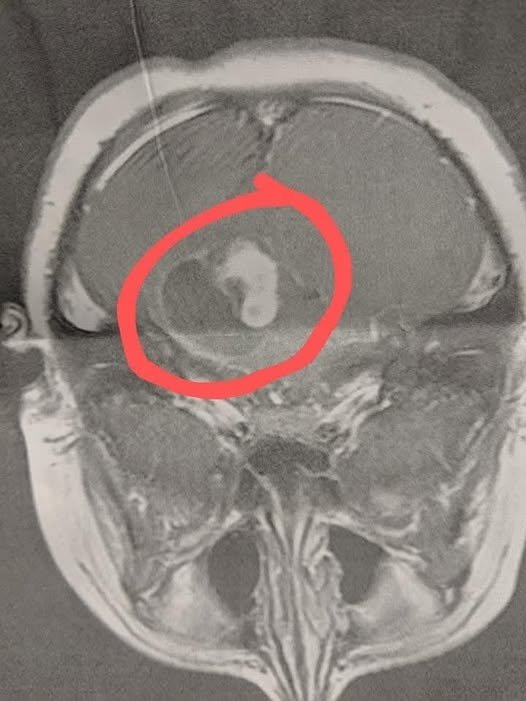

On the drive home, my phone rang. It was our pediatrician asking us to come in immediately for the results. My heart sank — I knew something was very wrong. When we arrived, the doctor showed us the MRI: a large brain tumor with fluid around it. Everything after that moved at lightning speed. We were sent straight to Duke Hospital, where my son underwent emergency brain surgery that same day.

The operation lasted eight long hours. The surgeons were able to remove about 90% of the tumor, but the remaining 10% was too close to the brain stem to remove safely. We were grateful he had made it through surgery, but we also knew the journey wasn’t over.